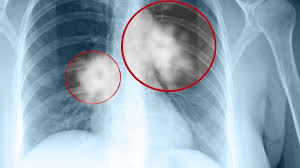

How Will I Know If My Lung Cancer Has Come Back : When Back Pain Turns Deadly An Unusual Presentation Of Lung Cancer Sciencedirect : It had been approved for my type of lung cancer, and with my particular type of cancer, was an option after chemo and radiation.. As for weakness in my arms, that's a tricky one to pin down. You will have exams, blood tests, and maybe other tests to see if the cancer has come back. When cancer cells from lung cancer have traveled to the liver and cause a secondary cancerous growth, you may have some of the following symptoms: Lung cancer is often not detected until it has spread. Weight loss is also almost universal, and it occurs even when people are eating a diet with adequate calories.

Wasn't a candidate for radiation. Sometimes fluid in the lungs can make breathing difficult and this could also be a sign of lung cancer. Gpod luck with your surgery recovery nic You will have exams, blood tests, and maybe other tests to see if the cancer has come back. If a lung cancer tumor is blocking a major airway, it could cause shortness of breath. Once you complete your treatments, expect to see your doctor at least every 6 months for the. Some cancer types have a higher risk of coming back. What recurrence means cancer recurrence means the cancer you originally had has come back. Lung cancer typically doesn't cause signs and symptoms in its earliest stages. Hi, i'm worried now just because her doctor was pretty adiment. Regional recurrence is when cancer recurs in the lymph nodes near the site of the original tumor. These appointments may include tests and scans. Signs and symptoms of lung cancer may include:

Knowing the type of your lung cancer is very important since it can play a key role in determining the treatment plan. The cancer is in the lymph nodes near the lungs. Exercise a fair bit nowadays which helps mentally and physically. Lung cancer is often not detected until it has spread. Sometimes fluid in the lungs can make breathing difficult and this could also be a sign of lung cancer. The steps below will help you know what you can expect from the lung cancer screening process. Some cancer types have a higher risk of coming back. As for weakness in my arms, that's a tricky one to pin down. In addition to providing unique insight on what it's like to battle and live with the disease, each story also provides reasons to be hopeful about the future of lung cancer research. If it is affecting both sides, you certainly don't need to worry about cancer. It had been approved for my type of lung cancer, and with my particular type of cancer, was an option after chemo and radiation. He said to her that it was cancer. Signs and symptoms of lung cancer typically occur when the disease is advanced.

The aim of this treatment is to try to prevent cancer from coming back. See your doctor if you have shortness of breath that concerns you. Once you complete your treatments, expect to see your doctor at least every 6 months for the. The doctor told me i was the perfect candidate. In addition to providing unique insight on what it's like to battle and live with the disease, each story also provides reasons to be hopeful about the future of lung cancer research. In general, depending on what stage of lung cancer you have, you will have a bunch of imaging up front, and then once a treatment plan is put into place, after that treatment has either been completed or started, you will be monitored, in general, regularly for. Sometimes fluid in the lungs can make breathing difficult and this could also be a sign of lung cancer. Your cancer care team will tell you what tests you need and how often they should be done. A new cough that doesn't go away Signs and symptoms of lung cancer typically occur when the disease is advanced. Cancer cachexia, a syndrome including unintentional weight loss and muscle wasting, is very common in the later stages of cancer. It may return in the area of the pancreas (recurrence) or spread to other parts of the body via the blood or lymph systems. Distant recurrence is when lung cancer recurs far away from the original tumor, such as in the bones, brain, adrenal glands, or liver.